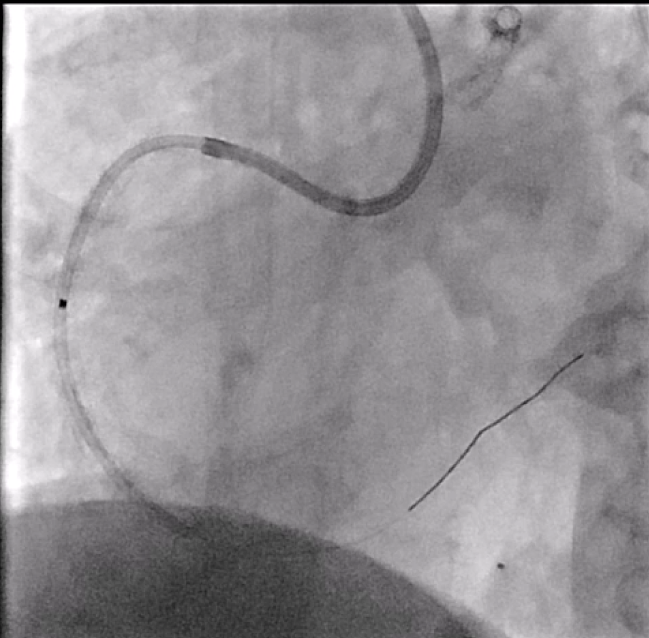

In view of severe left ventricular dysfunction, a 40cc IABP was inserted via the right common femoral artery for mechanical circulatory support during PCI. A 6Fr AL1 guide catheter was advanced via the right radial artery to selectively cannulate the right coronary artery (RCA). A Runthrough NS coronary guidewire was advanced into the distal R-PDA. Balloon angioplasty was performed from RPDA back to proximal RCA using a 2.5x15mm Sapphire3 NC balloon to 12atm. A Boston Scientific Opticross HD 60MHz IVUS catheter was advanced into the distal RPDA and intravascular imaging performed. Unfortunately, upon completion of the pullback run, the IVUS catheter could not be withdrawn. The IVUS catheter was stuck on the calcific and angulated segment in the proximal RPDA. Despite use of focused force technique, parallel ballooning, the IVUS catheter could not be withdrawn. During the attempts, the IVUS catheter inadvertently broke, leaving a short segment of the catheter in the RPDA. Check angiography showed no flow impairment. Thus, proximal to mid RCA was stented using a 3.0x38mm DES and a 3.5x48mm DES. Due to long procedural time, decision made to stage further PCI to the next day. The following day, PCI to LAD was performed uneventfully. The RCA was cannulated using a 7Fr AL2 guide catheter via right radial artery. A Sion Blue ES guidewire was advanced into the RPDA. A 6Fr Liquid guide extension catheter was advanced across the stented segments. A 3.2Fr EnSnare used to withdraw IVUS.

Case Summary

IVUS entrapment usually occurs on stent struts (distal edge, tortuous vessels, calcified lesions, small stent diameter). However, it can still happen in calcified and tortuous vessels. Follow the troubleshooting algorithm, do not forcibly pull. If the catheter breaks, can consider using such a snaring technique to retrieve. If all else fails, can perform CABG and removal of device.